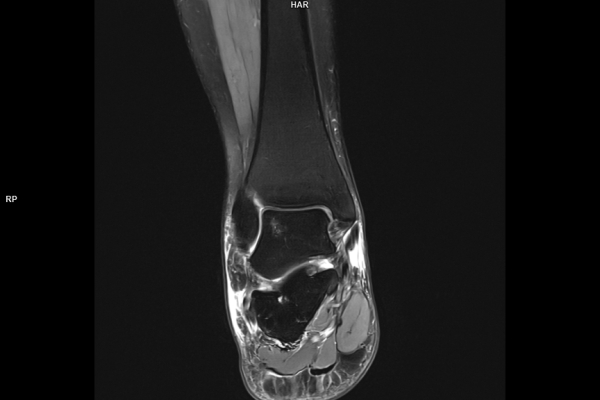

CT Untersuchung Bild

Detailbild MRT

Wir verbinden modernste Medizin mit einer Atmosphäre, in der Sie sich sicher und gut aufgehoben fühlen. Klare Abläufe, Ruhe und Zeit für Sie stehen im Mittelpunkt jeder Untersuchung. CT- und MRT-Bilder ohne Wartezeit. Mit Photon-Counting-CT und 3-Tesla-MRT setzen wir auf in Kärnten einzigartige Technologien für außergewöhnlich detailreiche Bilder und besonders präzise Diagnosen. Die schonenden Verfahren eignen sich auch für Kinder und Jugendliche. Kurze Messzeiten, große offene Geräte und ein ruhiges Umfeld sorgen für eine angenehme Untersuchung und ein gutes Gefühl von Anfang bis Ende.

Die MRT (Magnetresonanztomographie) arbeitet mit Magnetfeldern und Radiowellen und eignet sich besonders für Untersuchungen der Weichteile wie Gehirn, Muskeln oder Gelenke. Die CT (Computertomographie) nutzt Röntgenstrahlen und liefert schnelle, hochauflösende Bilder, insbesondere für Knochen, Lunge oder innere Organe. Die Wahl der jeweiligen Untersuchung richtet sich an das individuelle Krankheitsbild und wird bei der Überweisung festgelegt.